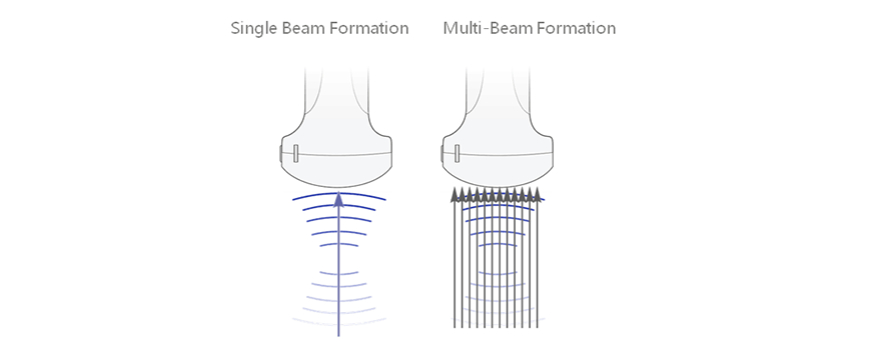

Multi-Beam Formation

Maximum 12 times tasking for one transmitted beam, resulting in excellent time resolution and higher frame rate.